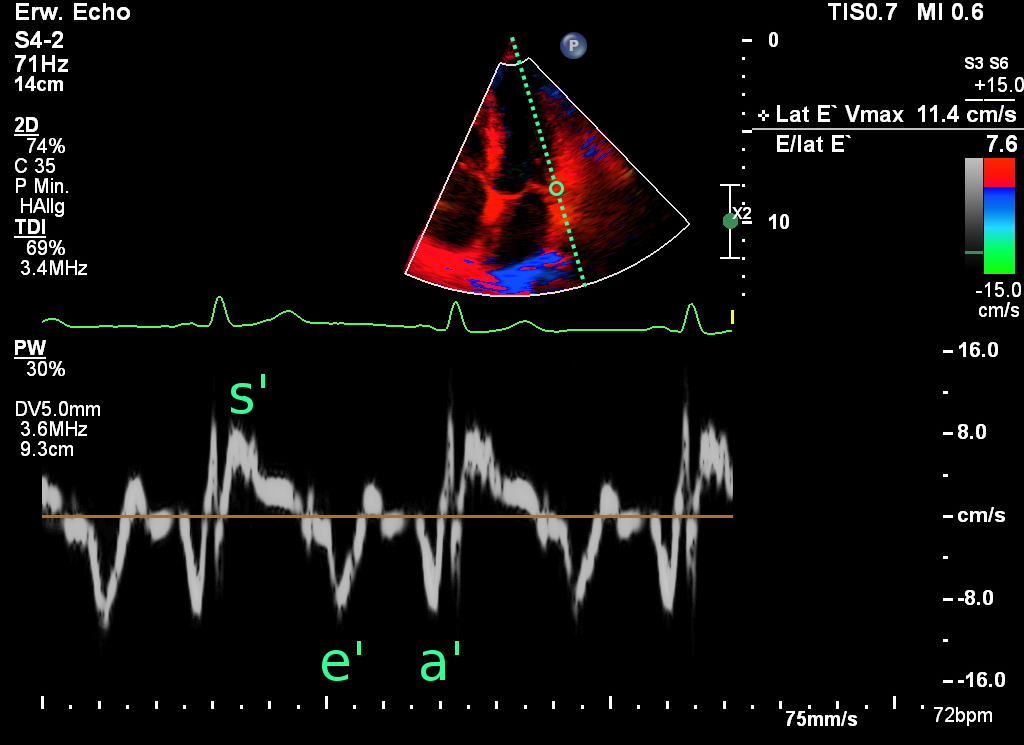

e‘lateral und e‘septal

Das im Gewebedoppler (Tissue doppler imaging = TDI) bestimmte e‘ spiegelt die maximalen Geschwindigkeit der frühen myokardialen Relaxation zu dem Zeitpunkt wider, an dem sich der Mitralanulus in der frühen schnellen LV-Füllung von der Apex entfernt. e' kann von apikal prinzipiell an jedem beliebigen Punkt des Mitralanulus abgeleitet werden, wobei die Bestimmung am lateralen (e‘lateral und septalen (e‘septal Anulus standardisiert ist. Aufgrund der unterschiedlichen Orientierung der Myokardfasern und der Nähe zu den kollagenen Fasern der Ventilebene sind die lateralen Werte etwas etwas höher als septalen.

Die Werte sind altersabhängig. Bei Kindern und gesunden jungen Erwachsenen kann e‘lateral >20 cm/s betragen. Bei Erwachsenen >30 Jahre ist e‘ >12 cm/s mit einer normalen diastolischen LV-Funktion assoziiert.12 Werte von e‘lateral <=8 cm/s deuten bei mittleren bis älteren Erwachsenen auf eine gestörte LV-Relaxation hin.11 Im Gegensatz zum Mitraleinströmmuster ist e' stabil gegenüber Änderungen des Füllungsdrucks.

Abb.: Die im Gewebedoppler bestimmten Geschwindigkeiten am lateralen Mitralannulus